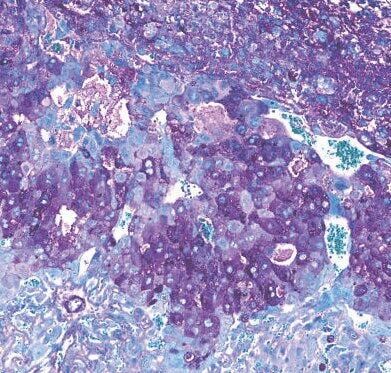

Over 150 biological processes in the placenta - involving over 400 different proteins - were found to be different in mice with, and without, Bifidobacterium breve in their gut. (Jorge Lopez-Tello/ Cambridge University via SWNS)

In the study, more than 150 biological processes in the placenta - involving over 400 different proteins - were found to be different in mice with, and without, Bifidobacterium breve in their gut.

Their placentas were also better at absorbing and transporting nutrients, such as amino acids and lactate, from mother to fetus.

The placentas of mice with Bifidobacterium breve in their gut also produced more of the hormones important for pregnancy, such as prolactins and pregnancy-specific glycoproteins.